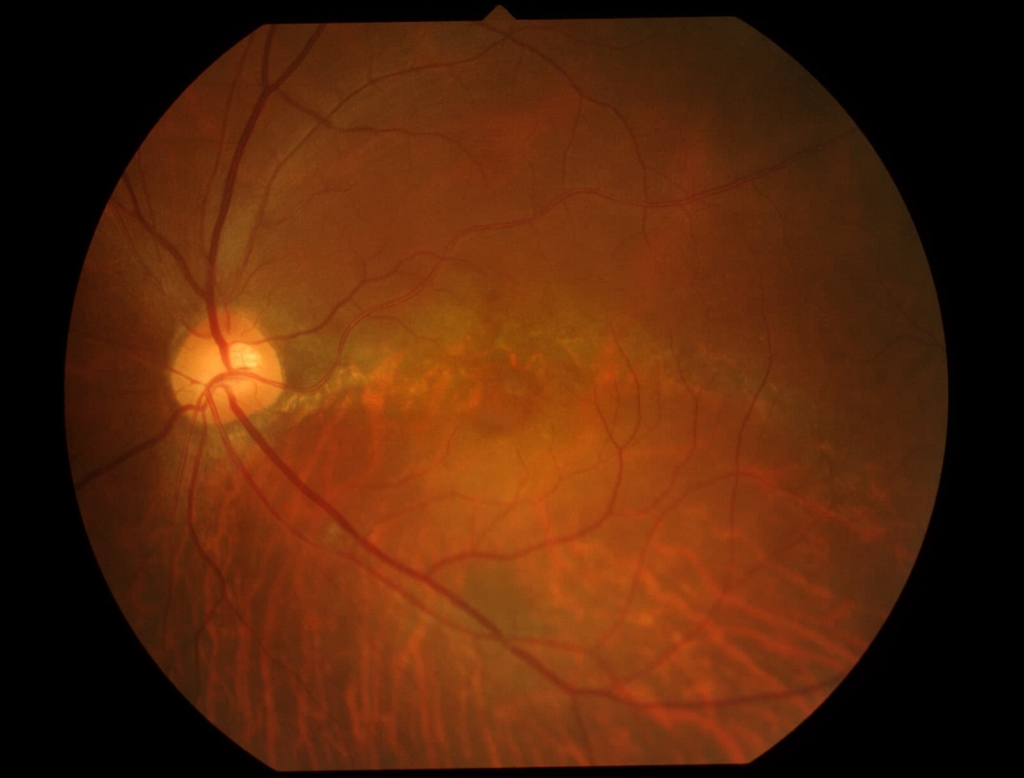

乳頭が下鼻側に傾斜し、下方に萎縮(PPA)がみられる。

両眼ともに、後部ぶどう腫staphylomaの上縁に一致して乳頭下縁から黄斑を横断するように帯状の網脈絡膜の萎縮巣がみられる。また後部ぶどう腫領域に一致して網膜・脈絡膜が菲薄化しているため、紋理眼底tessel lated fundusがみられる。

後部ぶどう腫の上縁に漿液性網膜剥離(SRD)がみられる。この後部ぶどう腫と正常部の境界付近に脈絡膜新生血管の発生を見ることもあるため、注意が必要。